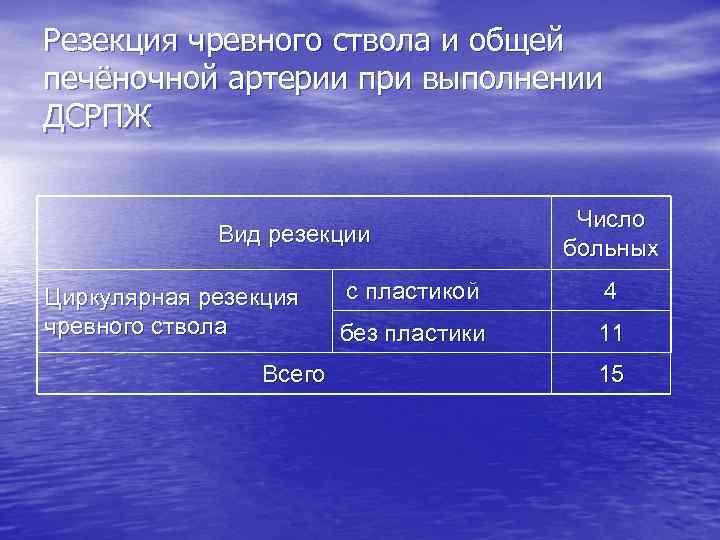

Резекция чревного ствола и общей печёночной артерии при выполнении ДСРПЖ Вид резекции Циркулярная резекция чревного ствола Всего Число больных с пластикой 4 без пластики 11 15